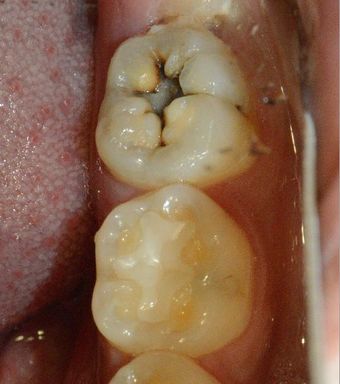

모든 충치는 치료를 해야 할까?

충치는 산성으로 인해서 치아의 구조가 무너지는 현상입니다.충치라고 무조건 치료를 하는것이 아닙니다. 충치도 종류가 있어요충치는 정지된 충치가 있고 진행되는 충치가 있습니다.우선 건강한 치아를 한번 볼께요 이 사진은 건강한 상태의 치아 입니다.이전에 레진 치료를 받은 흔적이 있지만 충치가 없는 상태의 치아에요.이 사진은 검은색으로 보이는 부위가 충치입니다.이 사진에도 치아를 따라서 보이는 검은 것이 충치에요.충치가 생겼을 때는 보시는 바와 같이 육안으로 확인할 수 있습니다.이렇게 검은색을 띠고 단단한 형태는 정지되어 있는 충치라고 볼수 있습니다.충치가 있는데 다시 석회화 되면서 충치가 더 진행이 되지 않는것이지요.이런 충치의 경우 충치니까 치료를 해야 하는것은 맞습니다. 하지만 진행이 되지 않고 정상적으로 기능을 하기 때문에 관리를 잘 한다면 치료를 보류해볼수 있어요.이 사진에도 충치가 보입니다. 치아는 외부는 검은식이지만 내부는 갈색을 보이는데 이런 형태의 충치는 진행이 되는 충치 입니다. 이런 식의 충치는 푸석푸석하며 치아의 구조가 약해져 있습니다.이런 진행중인 충치인경우에는 빠르게 치료를 해줘야 합니다.충치가 오래 진행이 되다보면 치아의 치질이 손상되게 됩니다.충치가 생긴 부위는 방사선 사진으로도 알수있는데요.우선 정상적인 치아를 한번 볼께요.왼쪽의 치아의 머리는 하얗게 생긴 정상적인 치아입니다.다음사진은 충치가 있는 사진인데요. 두개의 치아 사이에 검은 음영이 보이는데충치가 생겼을 때는 이렇게 방사선상에 음영으로 보이게 되요이 부분이 충치에 의해서 파괴된 부분입니다이 충치가 치아안의 신경까지 진행이 되지 않으면 신경치료를 안하고 간단하게 치료할 수 있는데충치가 신경까지 진행된 경우에는 통증을 느끼게 되고 염증이 생겨서 신경치료를 동반한 보철치료를 계획해야 합니다.충치는 신경에 도달하기 전까지는 통증이 없기 때문에 진행이 많이 되고 난 다음에 병원에서 뒤늦게 확인하는 경우가 많아요따라서 평소에 관리를 잘하고 이상이 없어도 치과에서 주기적으로 검사하는 것이 좋습니다.충치는 오랜기간에 걸쳐서 생기기 때문에 충분한 관심을 가지고 관리를 해주면 생기는 것을 방지 할수 있어요그럼 여러분의 구강내에 충치가 생기지 않도록 충분한 관심을 가지고 칫솔과 치실을 이용하여 꼼꼼하게 관리를 해주세요.여러분의 치아는 소중하니까요